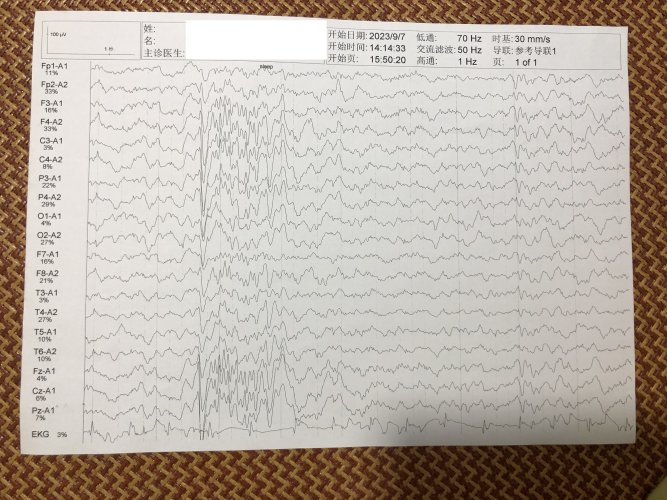

反馈下情况,孩子在国内的医院已经进行过一轮全面检测,没发现什么问题,但是现象是存在的。医生也没什么办法。医生说核磁共振和脑电图没问题,我们也不是很看得懂,各位如果懂的,请指点一下。另外进行了部分基因检测,没发现异常。下一步,我们国庆后打算去更权威的医院去碰碰运气。谢谢各位!